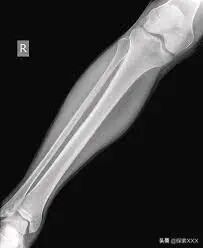

该案件引起了海地全国乃至一定程度上的国际关注。这名女子被送往一家政府医院,许多亲戚被逐一传唤以核实她的身份。X光检查显示,她的腿并没有断过,而且她的实际年龄与去世的那个居民的姐姐也不相符。因此可以断定,这并不是那个死去的人。